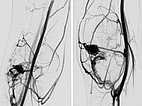

After renewed superselective catheterization of the AVM-feeding artery (lateral inferior genicular artery) ), the microcatheter is advanced to just before the nidus.

DSA image (roadmap technique) during re-embolization shows the freshly injected new additional embolic agent as black in the image.

Final DSA images (left AP, right lateral projection) after completion of repeat embolization again shows angiographically complete occlusion of both portions of the AVM.